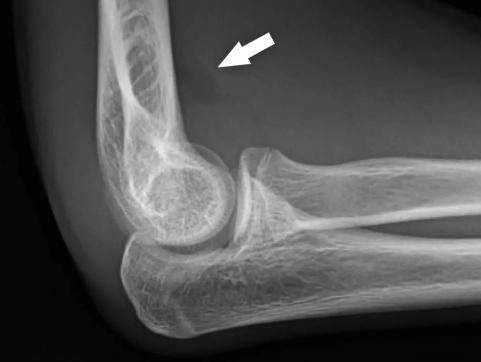

After an injury to the elbow, the joint X-Rays may show a ‘fat pad’ sign, which indicates swelling in the elbow joint and is often seen on X-Rays after a trauma in children. Sometime this can indicate the presence of a fracture, although in many cases there is no fracture seen. If your child has been diagnosed with a fat pad positive injury, they may not want to use their arm initially as it can be quite painful.